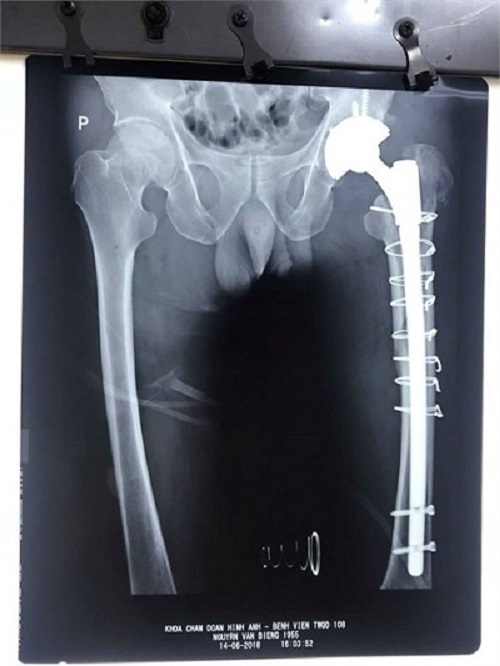

Hình ảnh X-quang sau phẫu thuật. Ảnh: Suckhoavadoisong.vn |

Xét nghiệm khi vào viện: thiếu máu nhẹ: hồng cầu: 2,95T/L, huyết sắc tố: 84g/L, suy chức năng gan: tiểu cầu thấp: 121G/L, men gan tăng, Bilirubin toàn phần, trưc tiếp tăng, albumin giảm, chức năng đông máu kéo dài: Prothrombin: 55%, siêu âm: dịch cổ chướng, trên hình ảnh X-quang: lỏng chuôi khớp háng nhân tạo, gãy toác đầu trên xương đùi trái.

Sau 15 ngày điều trị tích cực, bệnh nhân được tiến hành phẫu thuật thay khớp háng . Sau 3 giờ phẫu thuật, 1 giờ theo dõi tại phòng hồi tỉnh, bệnh nhân được chuyển về Khoa Phẫu thuật khớp.